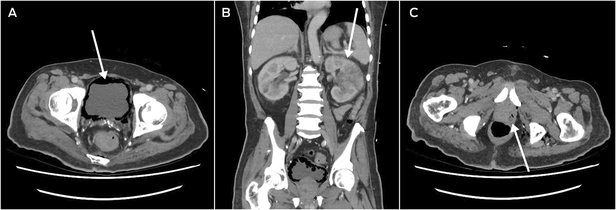

He returned to hospital six weeks after discharge from the Australian hospital, after being found unresponsive at home, with a preceding two‐week history of lethargy, fatigue, and anorexia. He was in septic shock with a temperature of 39°C, tachycardia, tachypnoea, and a Glasgow Coma Scale score of 10. CT scan revealed severe emphysematous cystitis (Box 2, A), left‐sided pyelonephritis (Box 2, B), prostatic abscess (Box 2, C), and gas within the lower pelvis. Operative source control with complete urinary exenteration was deemed not survivable. He was admitted to the intensive care unit, catheterised, and treated with IV meropenem, vancomycin and clindamycin. The infectious diseases team reviewed him within 24 hours of his admission, identifying his epidemiological risk factors for hypervirulent K. pneumoniae. Urine and blood cultures grew K. pneumoniae noted to have a hypermucoviscous phenotype (positive string test), following which his antibiotic regimen was rationalised to high dose IV ceftriaxone monotherapy. After initial clinical improvements, his condition deteriorated with new fevers, worsening confusion, and rising inflammatory markers and lactate on his blood tests, and IV metronidazole and ciprofloxacin were added. He gradually improved, receiving a further six weeks of oral ciprofloxacin monotherapy.